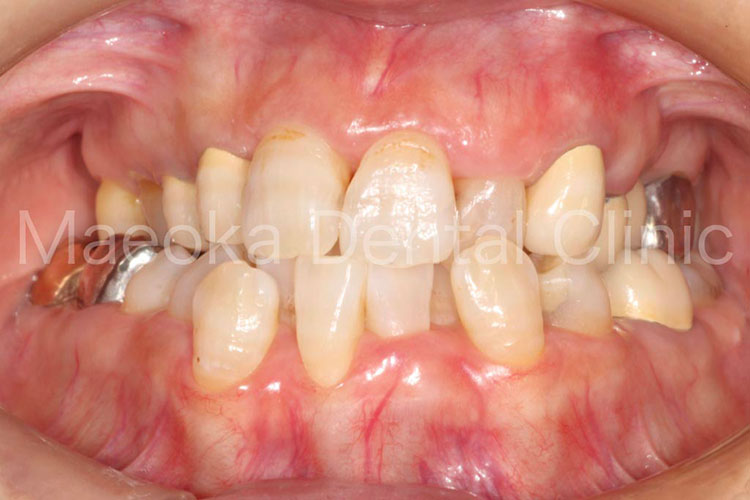

患者さんは49歳女性の方で、「全体的にしっかりと治したい」という主訴で来院されました。

出産を機にお口の環境が悪くなっていったとのことでしたが、勇気が出せずになかなか歯科を受診できなかったそうです。

診査を行うと奥歯の噛み合わせが失われており、審美面、機能面ともに大掛かりな介入が必要な状態でした。

はじめに患者さんから伺った情報を基に、現在の環境になってしまった根本的な原因を模索し、原因除去を行っていきました。その後、歯の移植(右下5を右上3に移植)、部分的な矯正などを行った上で審美的な範囲はセラミックスを用いた被せ物、歯の削除量を最小限にするために見えない箇所は金属を用いた被せ物で最終的な修復を行いました(一部表面的な虫歯は残っていますが、患者さんと相談した上で、今の段階で積極的に削ることは避け、経過観察を行うこととしています)。

プロビジョナルレストレーション(精密な仮歯)を入れた上で機能上問題ないことを確認するなどチェック期間にも時間を要したため、5年に及ぶ治療期間を要しましたが、残りの患者さんの人生の長さを考えると必要十分な治療であったと考えます。

保存不可能と思われる歯が多数ある中ではありましたが、結果として抜歯に至った歯は3本のみで、インプラントを用いることなく、患者さん自身の歯でお口の環境を再構築することができました。

今後はメインテナンスで治療終了時の環境を長期的に維持できるように努めていきます。

治療前(正面)

治療後(正面)